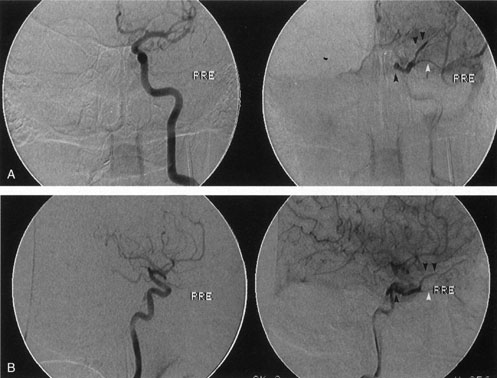

If the clinical suspicion is very high for an arteriovenous fistula, particularly if intervention is required, bilateral selective arteriography of the internal and external carotid arteries is indicated. This shows retrograde opacification of the cavernous sinus and the involved venous drainage system (Fig. 17). A difference in the ocular pulse amplitude (OPA; i.e., the difference between the maximum and minimum intraocular pressure during the cardiac cycle) between a patient's two eyes of more than 1.6 mm Hg may be useful to identify patients with either direct or indirect arteriovenous fistulas.124 This is performed by instilling a topical anesthetic drop into each eye, instructing the patient to look at the 20/400 “E” on a projected Snellen chart, and placing a pneumotonometer tip on the central cornea for 10 to 15 seconds. The difference in OPA between the two eyes then is calculated from the intraocular pressure curves. Ultrasound, CT, and MRI are neither sensitive nor specific. A-scan orbital ultrasonography and Doppler illustrate venous distention and dynamic flow. Color Doppler ultrasonography shows enlargement and arterialization of the venous flow (blood flow reversal), as well as enlarged extraocular muscles and may be useful in monitoring the clinical course of arteriovenous fistulas.109,125 Reversal of flow in the superior ophthalmic vein is not pathognomonic for arteriovenous fistula: It also has been described in carotid sinus thrombophlebitis, orbital apex tumors, and in normal persons.126 Computed tomography demonstrates enlargement of the superior ophthalmic vein and frequently enlargement of the extraocular muscles proportional to the degree of shunting (Fig. 18). There may be CT evidence of venous thrombosis in the form of a nonenhancing defect in the lumen of the superior ophthalmic vein or cavernous sinus. Magnetic resonance angiography (MRA) also may be used to evaluate these lesions, but false-negative results can occur.109

Fig. 17. Left internal carotid angiogram. The internal carotid artery within the cavernous sinus is seen in anteroposterior projection as a dark circle (A) and in lateral projection as an S-shaped structure (B). The fistula (black arrow) in this patient drained anteriorly into the superior ophthalmic vein (double arrow) and inferior ophthalmic vein (white arrow). In the absence of a history of trauma, the presumed etiology of the fistula in this patient was rupture of a preexisting intracavernous aneurysm.

Fig. 18. Direct arteriovenous fistula. Axial computed tomography scan of this patient showing the enlarged left superior ophthalmic vein (white arrow). The rectus muscles of the left orbit were all diffusely enlarged.